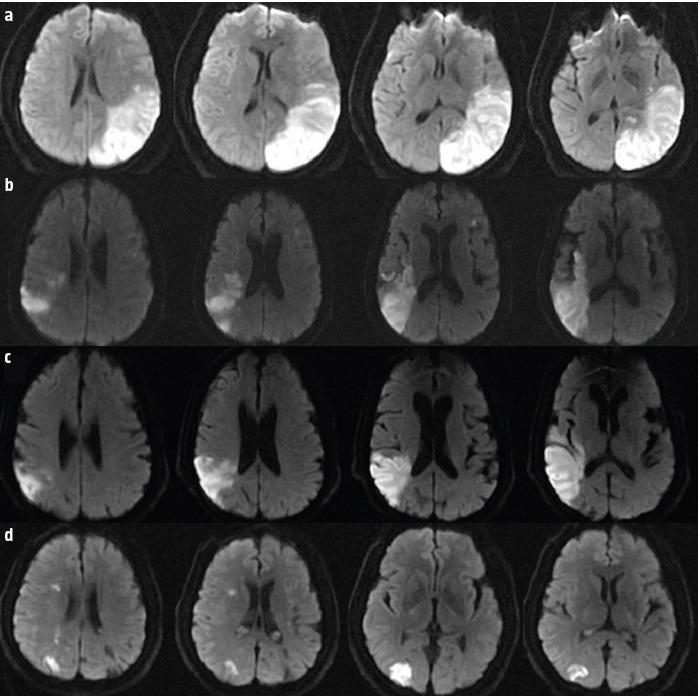

Four patients presented after sudden-onset gait lateropulsion. On neurological examination, all patients had at least one cortical sensory deficit and wide-based gait with lateropulsion towards the side of the cortical deficit. Neuroimaging revealed a subacute parietal lobe stroke contralateral to the side of gait lateropulsion. In two patients we found bilateral lateropulsion with predominance towards the side of cortical deficit and increase of unsteadiness with eye closure (an apparent Romberg sign), with neuroimaging revealing bilateral parietal strokes (subacute contralateral and chronic ipsilateral to gait lateropulsion).

4 例患者出现突发性步态侧方偏倚。在神经学检查中,所有患者均至少存在一处皮质感觉缺失和宽基底步态,并伴有向皮质缺失侧的侧方偏倚。神经影像学显示与步态侧方偏倚侧相对应的亚急性顶叶中风。在 2 例患者中,我们发现双侧侧方偏倚,以皮质缺失侧为主,并伴有闭眼时不稳定性增加(明显的 Romberg 征),神经影像学显示双侧顶叶中风(亚急性对侧和慢性同侧与步态侧方偏倚)。